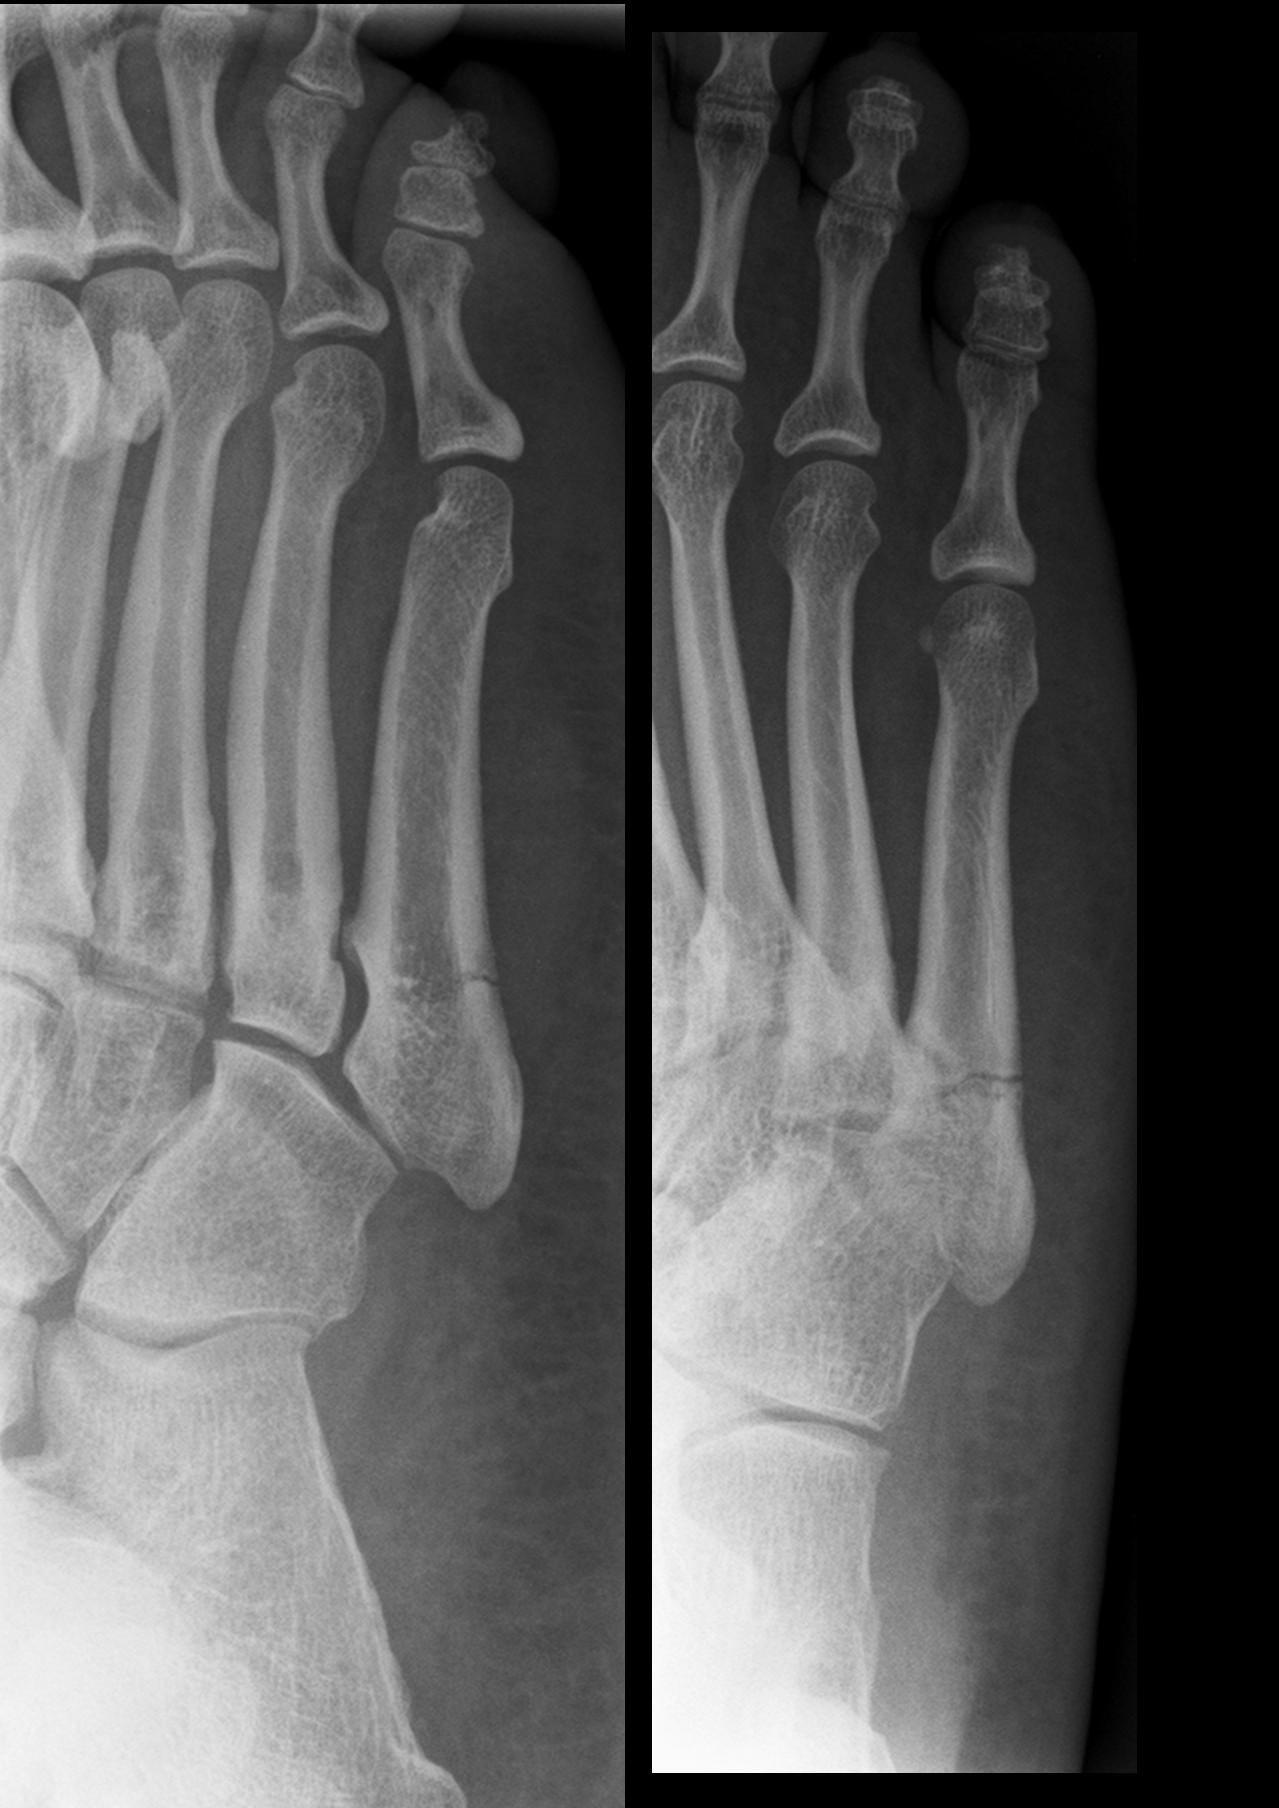

The Jones Fracture is named after a British Orthopaedic surgeon, Sir Robert Jones. He was the first to describe the fracture in the foot that occurs in the base of the 5th metatarsal bone on the lateral aspect of the foot. The fracture is thought to occur secondary to the accumulation of stress and pressure that is placed on that part of the 5th metatarsal. The compression and sheer forces that are placed on that part of the bone are enormous in some people and body weight and activity level can pre-dispose them to the Jones Fracture.

The bone accepts most of the body’s weight during gait and the Peroneus Brevis muscle inserts to that part of the metatarsal. The muscles strong contracting force to help stabilize the foot / ankle from the lateral side can increase the pressure applied to the base of the bone. The fractures are described by the area that they occur and it is one of three zones of the metatarsal. The first zone is a “chip” or avulsion fracture and treated conservatively in a cast or boot. The fracture that occurs at the junction of the base and the shaft it is in zone 2 and it might be fixed surgically. Lastly, a fracture in the shaft or zone 3 can take a very long time to heal and is frequently treated by performing surgery.

Unfortunately, these fractures don’t usually heal quickly. The difficulty and delayed healing has lead most surgeons to perform surgery on the bone and fixate it with hardware. The person is then required to remain non-weight bearing until adequate healing has taken place (usually 4-6 weeks) which is determined by an X-ray. When the enough healing has occurred the person is allowed to transition to full weight bearing while wearing a controlled ankle motion boot or CAM. These boots have been shown to reduce the amount of stress and pressure that is placed on the fracture site. These boots can be removed so the patient can also begin a Physical Therapy rehabilitation program.